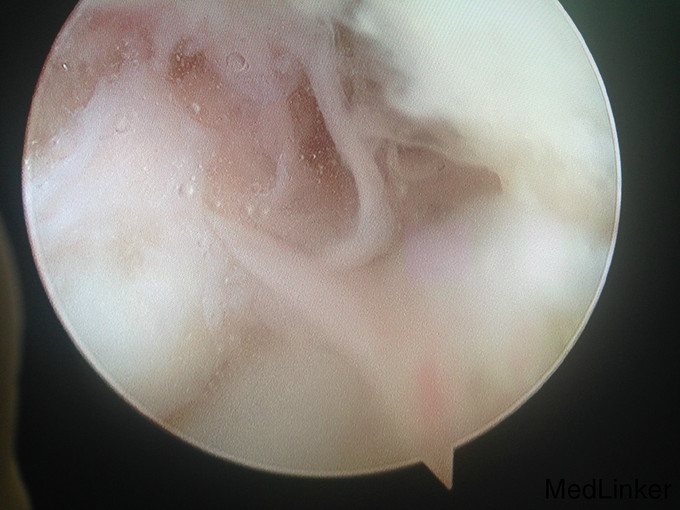

左踝扭伤后肿胀疼痛伴活动受限半年

查体:左腓肠肌萎缩,左踝轻度肿胀。左踝关节ROM较对侧降低,以背伸活动受限最明显。距腓前韧带处未及明显压痛。左踝内、外侧关节间隙压痛(+)。ADT(-),外侧应力试验(-)。左下肢肌张力正常、感觉正常。 辅检:MRI示“左踝关节积液”

诊断:左踝关节创伤性滑膜炎 治疗:左踝关节镜下滑膜清理、胫骨前缘成形

随访:患者术后即刻踝关节活动度恢复正常,2周恢复正常行走。 讨论:踝关节扭伤很常见,扭伤后会发生各种各样的情况。此患者扭伤后继发了滑膜炎,并伤及了关节软骨。这种情况应进行关节镜手术治疗。此外,核磁共振对关节疾患的诊断也是有限的,关节镜才是黄金标准。